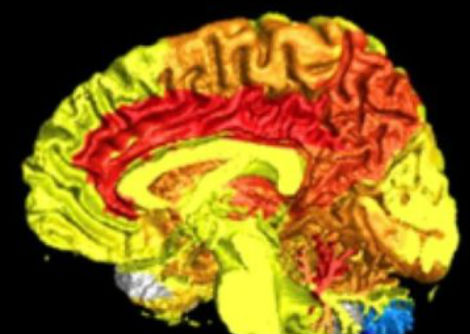

الحمل له تأثيرات عديدة على الجسم

كما يعلم كل من يمرّ بالحمل، يُحدث الحمل تحولات هائلة في الجسم، والآن لدينا الصورة الأكثر تفصيلاً حتى الآن لكيفية تأثيره على الدم والأعضاء والجهاز المناعي أسبوعيًا. قد يُساعد هذا في توفير علاجات ما بعد الحمل، بالإضافة إلى الكشف عن مخاطر الإصابة ببعض الأمراض أثناء الحمل.